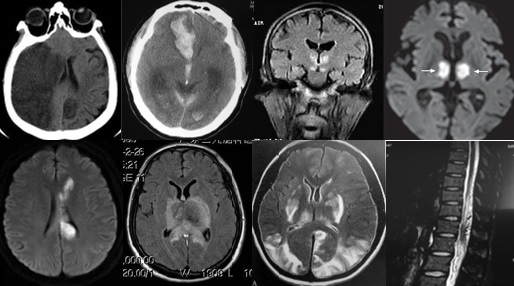

重要申明:以下每个部分会配磁共振图片,因疾病和影像之间存在同病异象、同像异病,为避免误导,图片不标注疾病,请各自鉴赏,另其中有部分图片来源于网络,有疑问可与本人联系。

T--toxication,中毒/trauma,外伤。

个人认为这里的中毒理解为毒物相关的病变更合理一些。

如酒精中毒相关的,如MBD。

各种中毒,有机溶剂,如苯、甲醇、一氧化碳中毒、氨己烯酸中毒等。

*品毒**如*洛因海**、*卡因可**等。

抗肿瘤或免疫*制剂抑**如甲硝唑、5-FU(5-氟尿嘧啶)及其前体药物卡培他滨、他克莫司、甲氨蝶呤、贝伐单抗等相关性脑病。

S--stroke,卒中,即血管性

各种动脉性、静脉性血管病、静脉窦血栓形成、动脉夹层致脑梗塞、脑小血管病、脑动静脉畸形、CAA等,Moya-Moya也可出现脑实质的多发病灶,易被误诊为脱髓鞘。